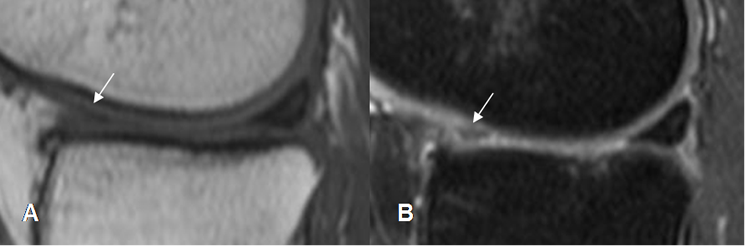

Fig 83. Resección meniscal parcial.

A: RM sagital y B: RM coronal en T1. Cuerno posterior del menisco interno mas pequeño, por menisectomía parcial. Adicionalmente hay lesiones osteocondrales el en platillo tibial y el cóndilo femoral.